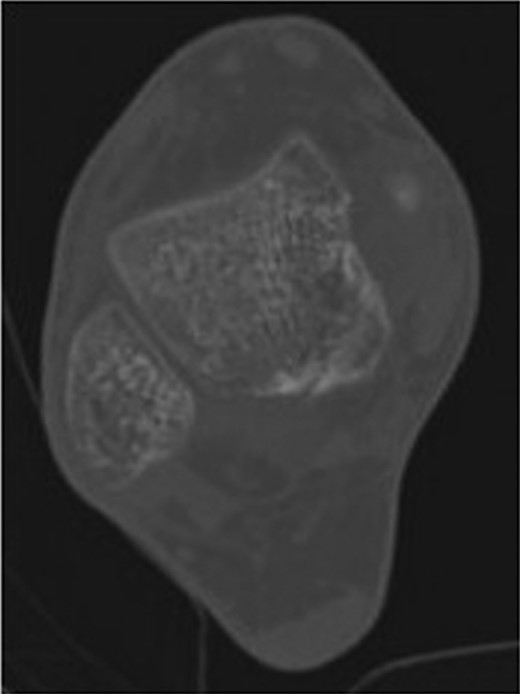

The patient subsequently underwent a manipulation under anaesthesia and POP application of his left distal tibia and right ankle to correct the talar displacement. Despite this, post-operative radiographs of the right ankle showed persistent widened medial tibio-talar joint, and the patient developed considerable right ankle pain and soft tissue swelling which did not correspond with the initial radiograph findings. Magnetic resonance imaging (MRI) of the right ankle joint was performed which revealed extensive marrow oedema through the medial malleolus epiphysis and the medial body of the talus. There was evidence of disruption of the medial cortex of the talus which explained the widened medial tibio-talar joint (Fig. 2). No disruptions of the epiphyseal plates or ligamentous structures were identified. The injury around the tibio-talar joint was identified as an undisplaced fracture through the postero-medial talus with a corresponding ‘kissing’-type lesion of the inner surface of the medial malleolus with gross soft tissue oedema. In view of the overlooked skeletal injury, a further computer tomography (CT) scan of the ankle joint was performed which confirmed a fragmented undisplaced fracture of the postero-medial aspect of the talus, with the anterior subtalar joint remaining intact and an undisplaced fracture through the medial malleolus (Fig. 3).

Right ankle CT axial view demonstrates undisplaced compression fracture of the medial body of the talus.